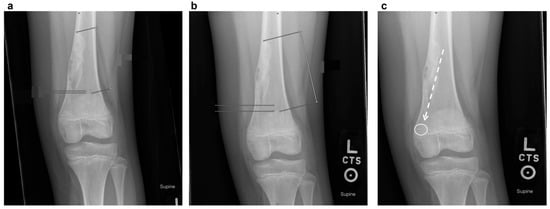

- Curettage and Bone Grafting: This is by far the most performed procedure. After curettage, the cavity is filled with autograft, allograft, or synthetic bone substitute [32]. While autograft is theoretically biologically superior, the donor site morbidity makes allograft the most used graft choice. In addition, the relatively high success rate and low risk of recurrence make the risks of an additional incision with autograft prohibitive. Synthetic substitutes such as calcium sulfate and calcium phosphate can provide structural support to allow earlier weight bearing. Again, the risks of cementation, in the setting of a benign disease with good operative results, make this a less common choice. Adjuvants are typically not used in the curettage stage for NOFs, as they are in giant cell tumors of bone or aneurysmal bone cysts. NOFs are not locally aggressive, and the use of phenol or argon beam coagulation is not typically indicated to reduce recurrence. Phenol and argon have a risk of local tissue damage, making them uncommonly used in the setting of NOFs. Figure 5 demonstrates pre-, intra-, and post-operative radiographic images of a 17-year-old boy with a large symptomatic distal tibia NOF who underwent a curettage and bone grafting procedure.